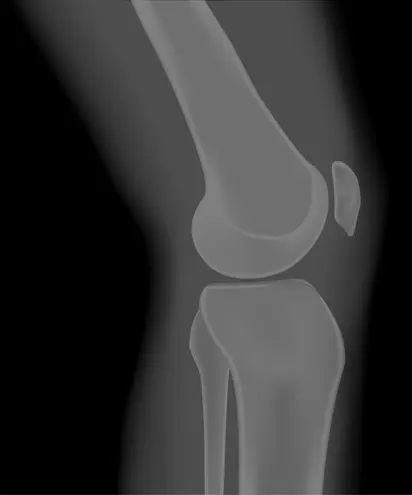

Your knee is divided into three major compartments Ghoota's expertise and the hospital's dedicated team. The medial compartment (the inside part of the knee), the lateral compartment (the outside part), and the patellofemoral compartment (the front of the knee between the kneecap and thighbone)

In a unicompartmental knee replacement, only the damaged compartment is replaced with metal and plastic.

Partial knee replacement is a surgical option if your arthritis is confined to a single compartment of your knee Unicompartmental knee replacement is a minimally invasive surgery in which only the damaged compartment of the knee is replaced with an implant. Exercise resources testimonials, videos, podcasts and more Knee partial knee replacement surgery this video shows a partial knee replacement surgery